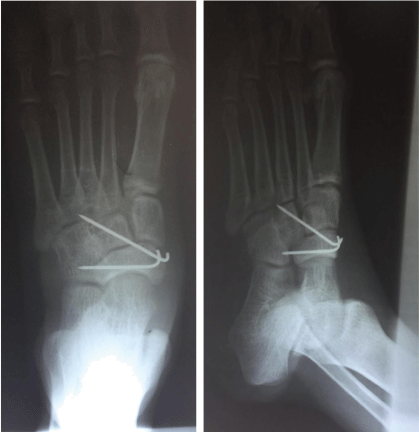

Postoperative day five was uneventful and a control radiograph showed anatomical reduction of the navicular bone (Figure 3). The patient was discharge on analgesics, and was advised not to bear weight on the affected foot. A follow-up visit was scheduled one week later, during which the patient was pain free and the physical examination was unremarkable. Another follow up visit was scheduled twelve week later the patient had no complaint, the physical examination was normal and the X-ray was unremarkable (Figure 4). We therefore plan to removed Kirschner wires after seven weeks, but unfortunately, the patient was see after 12 weeks and after that he was lost to follow up.

Figure 3: Post-operative X-ray at day 5 showing a normal talonavicular joint, with two K-wires maintaining the navicular bone in place. View Figure 3

Figure 4: Post-operative X-ray done after 12 weeks showing a normal talonavicular joint, with two K-wires maintaining the navicular bone in place. View Figure 4